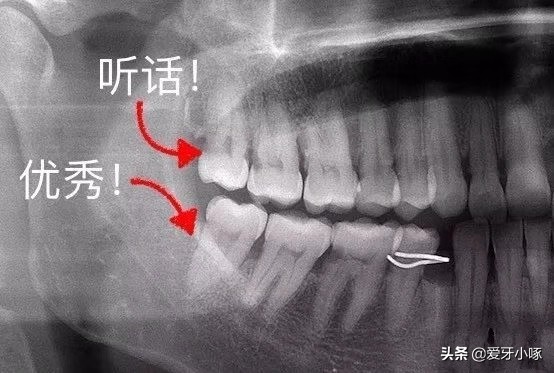

这种智齿完全长出来了,不但长得很正,而且上下咬合都很好,既没有出现牙疼又没有炎症的情况是可以不拔的!

但是呢,不是每个人都有这么好的运气滴~更多的是不听话的!不但疼还是刻骨铭心的疼!比如这种